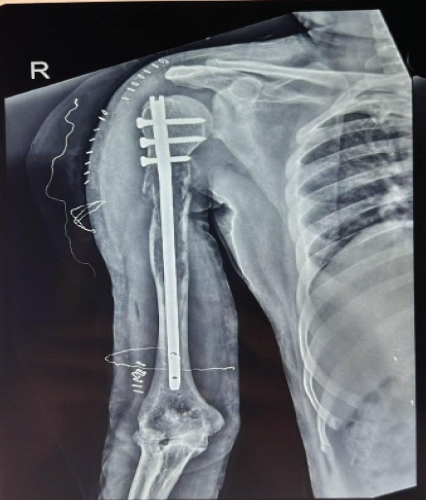

Investigation

Radiograph of right arm shows pathological fracture of right shaft of humerus (Fig. 7).

Figure 7 : Plain radiograph of the right arm showing pathological fracture of the right shaft of humerus (55-year-old male with multiple myeloma for 3 years). The lytic lesion at the humeral shaft demonstrates tumor involvement characteristic of multiple myeloma-related pathological fracture.

Intervention

Patient was managed with closed reduction and internal fixation using IM humerus nailing (Fig. 8) along with biopsy.

Figure 8 : Postoperative radiograph of the right humerus following closed reduction and internal fixation using intramedullary humerus nailing. The locked intramedullary nail secures the pathological fracture, enabling functional recovery and pain relief. The minimally invasive approach minimizes soft tissue trauma and operative morbidity.

Outcome